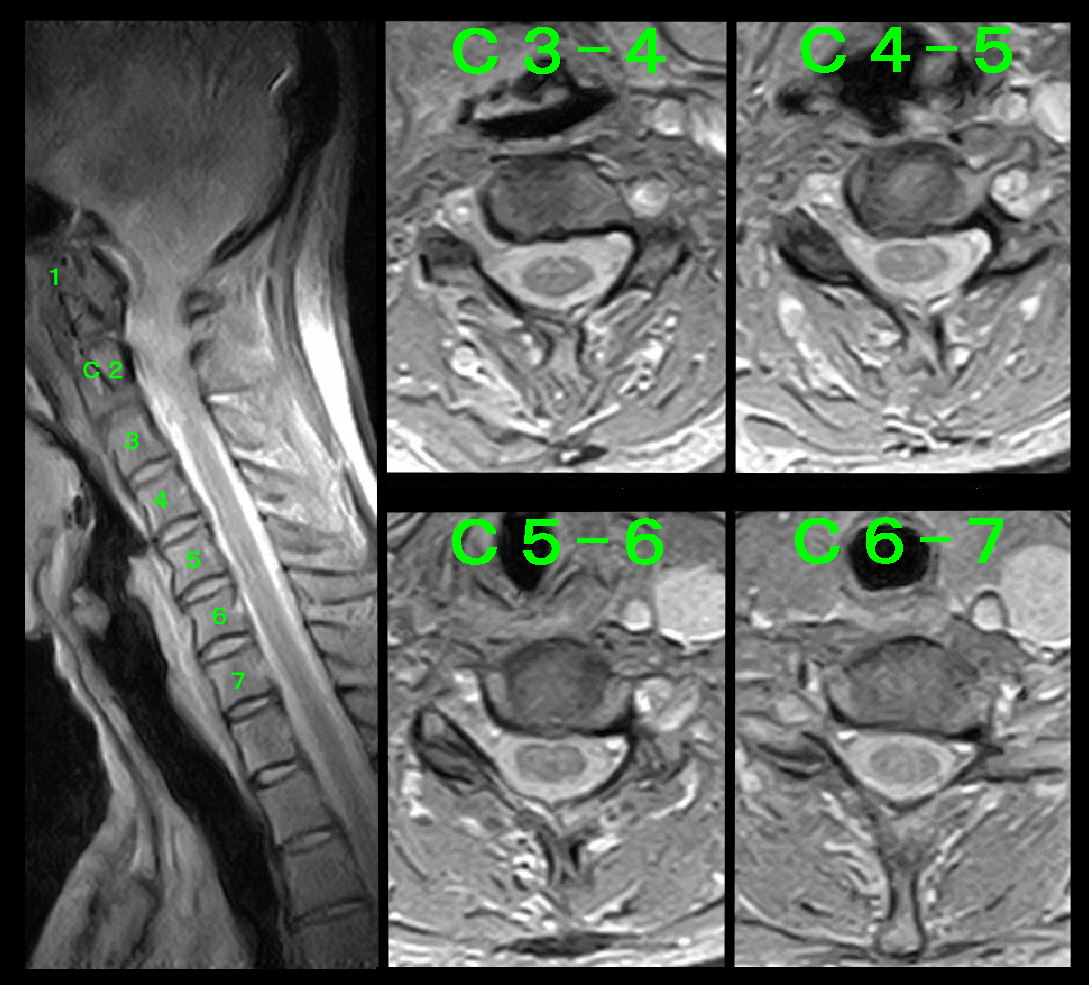

当院では自動車事故(自賠責)の診療では、MRI検査を原則施行しています。

7月27日(初診5日後)に行った頚椎のMRI検査では患者さんの症状の原因となるような所見は確認されませんでした。

MRHW.jpg